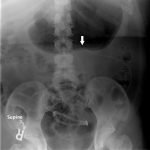

An immediate post-op abdominal x-ray performed after the patient’s VP shunt revision 30 days prior to this ED visit reveals the VP shunt tip in the mid abdomen. A CT of the abdomen performed on the day of the ED visit reveals the VP shunt tip interposed between the spleen and the diaphragm.